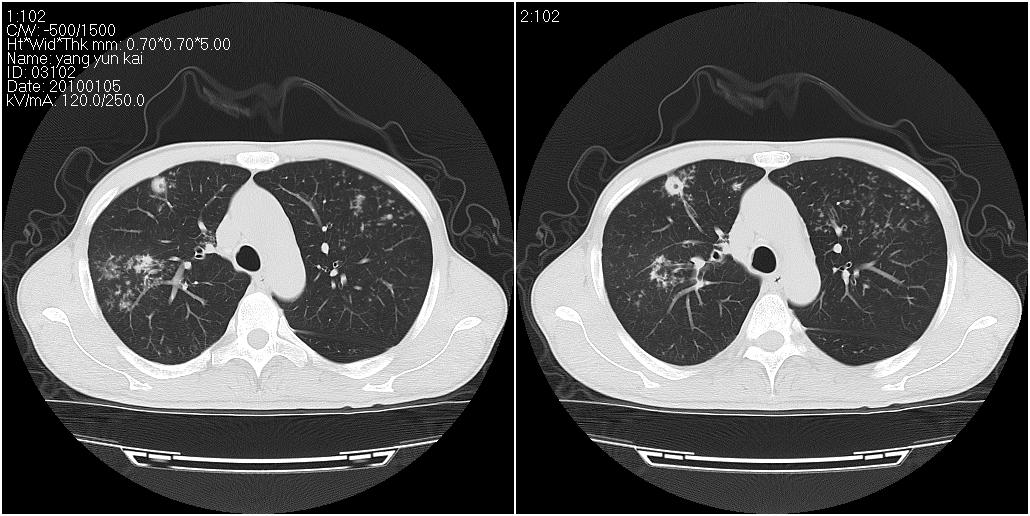

标题: CT23980:男性,47岁。近来咳痰、咳血,血沉增快(40左右),

男性,47岁。近来咳痰、咳血,血沉增快(40左右),痰中未检出结核杆菌。

两肺继发性肺结核并多发性结核球形成,部分病灶内空洞形成。